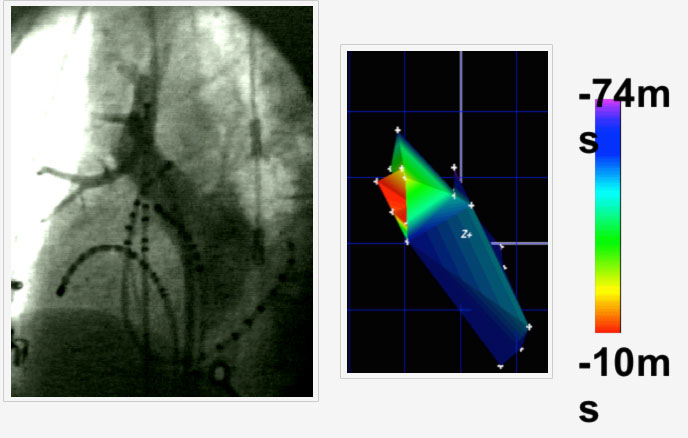

Figure: Pulmonary venogram (left) with multiple catheters in the right upper pulmonary vein (RUPV) The trigger for AF within the PV was mapped and shown in red in the left panel as the site of earliest activation of AF.